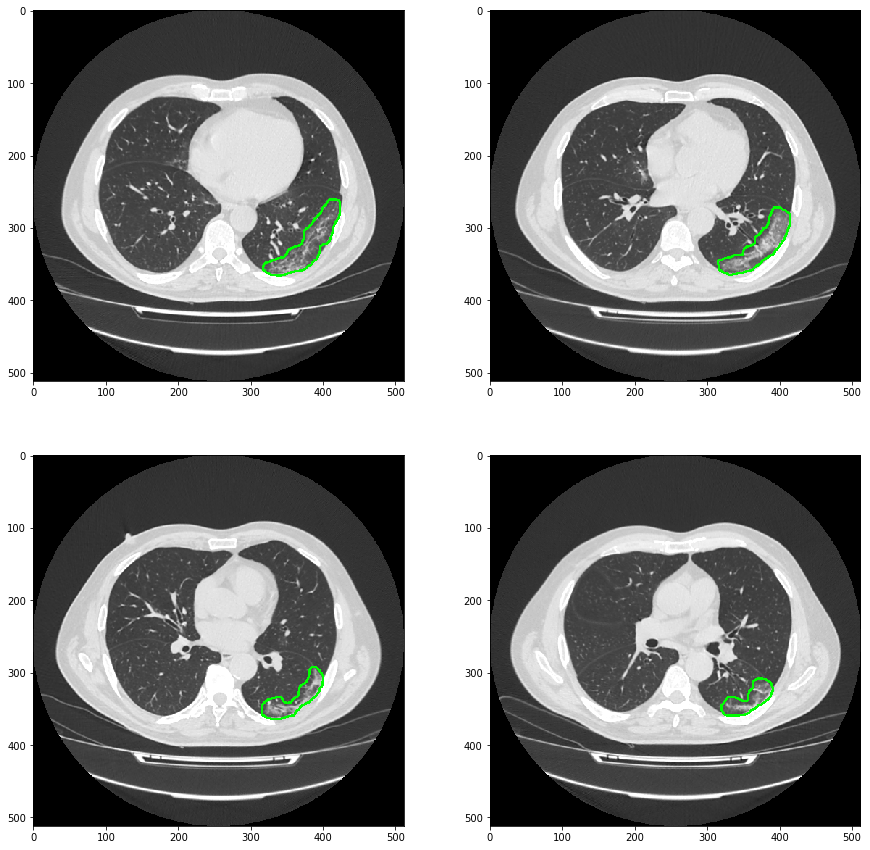

最终结果 结合PyQt制作病灶检测小工具

模型检测效果如下图:

结合PyQT制作小工具效果如下图:

对预测结果进行展示

可见模型对磨玻璃样病灶的细节分割并不是很好。但是这个项目的目地只是需要通过预测的mask结果在原图上画出病灶的轮廓,实现对病灶的检测和定位。告诉医疗那一层有磨玻璃样病灶,或者告诉医生那一层出现的磨玻璃样病灶面积是最大的。

plt.figure(figsize=(15, 15))

plt.subplot(221);plt.imshow(result[20])

plt.subplot(222);plt.imshow(result[22])

plt.subplot(223);plt.imshow(result[24])

plt.subplot(224);plt.imshow(result[26])

plt.show()